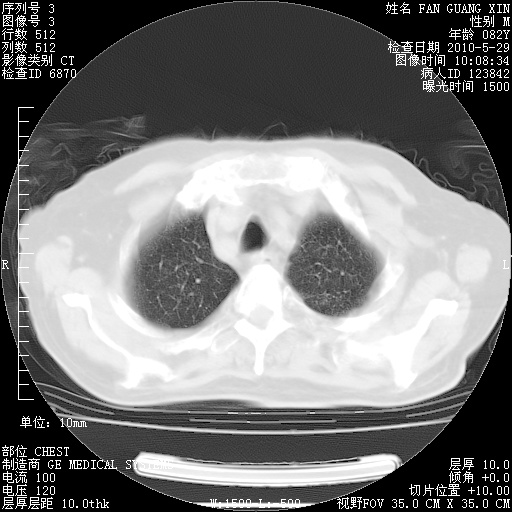

还需要哪些辅助检查?我们医院排除真菌感染没有任何检验方法,胸片好像能够排除肺部真菌感染。

CD3+ T细胞/淋巴细胞 46% (参考值50.00~84.00%)

CD3+CD4+ T细胞/淋巴细胞 21% (参考值27.00~51.00%)

CD3+CD8+ T细胞/淋巴细胞 25% (参考值15.00~44.00%)

CD3+CD4+ T细胞/CD3+CD8+ T细胞 0.84 (参考值0.71~2.78)

T细胞亚群是治疗5天采血。